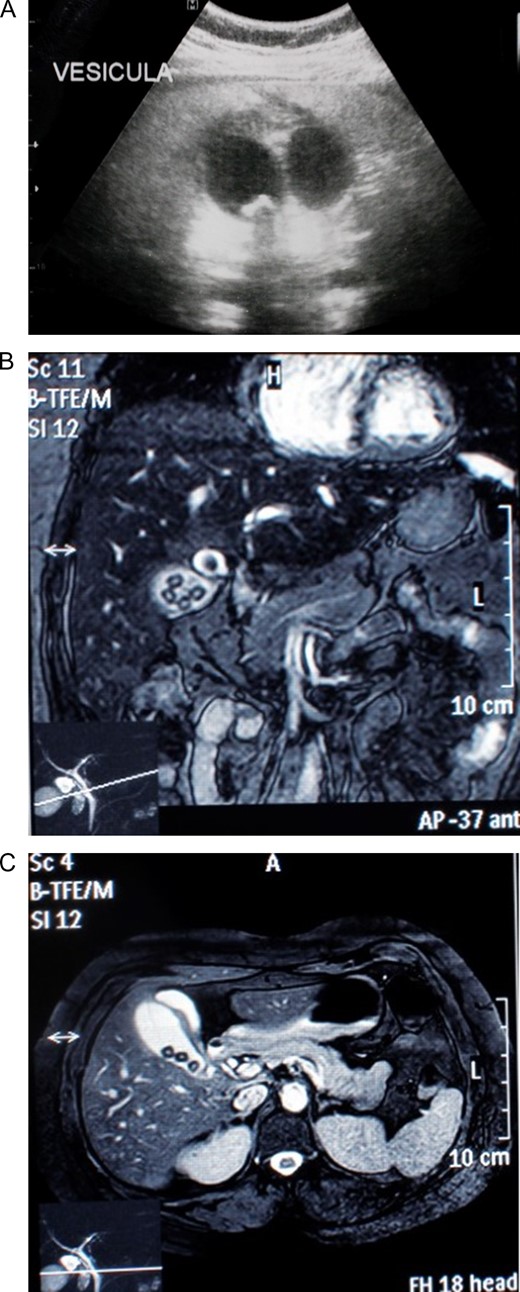

Laboratory data found elevated white blood cell count and a positive C-reactive protein. Bilirubin, liver function tests and amylase were normal. Due to pain, an abdominal ultrasound was requested that revealed two gallbladders. Two piriform images, with anechoic content, were detected. The left one had gallstones and right one had biliary sludge, also the right gallbladder had a thickened echogenic 4.5 mm wall (Fig. 1A). A magnetic resonance cholangiopancreatography confirmed this diagnosis. It revealed a normal liver and a gallbladder duplication with inflammation signs in one of them (Fig. 1B), they both had independent cysts ducts that joined in a common cystic duct before entering a normal diameter common bile duct (Fig. 1C).

(A) Abdominal ultrasound revealing two gallbladders. (B) A magnetic resonance cholangiopancreatography revealing a normal liver and a gallbladder duplication with inflammation signs in one of them. (C) A magnetic resonance cholangiopancreatography revealing a gallbladder duplication with independent cysts ducts that joined in a common cystic duct before entering the common bile duct.